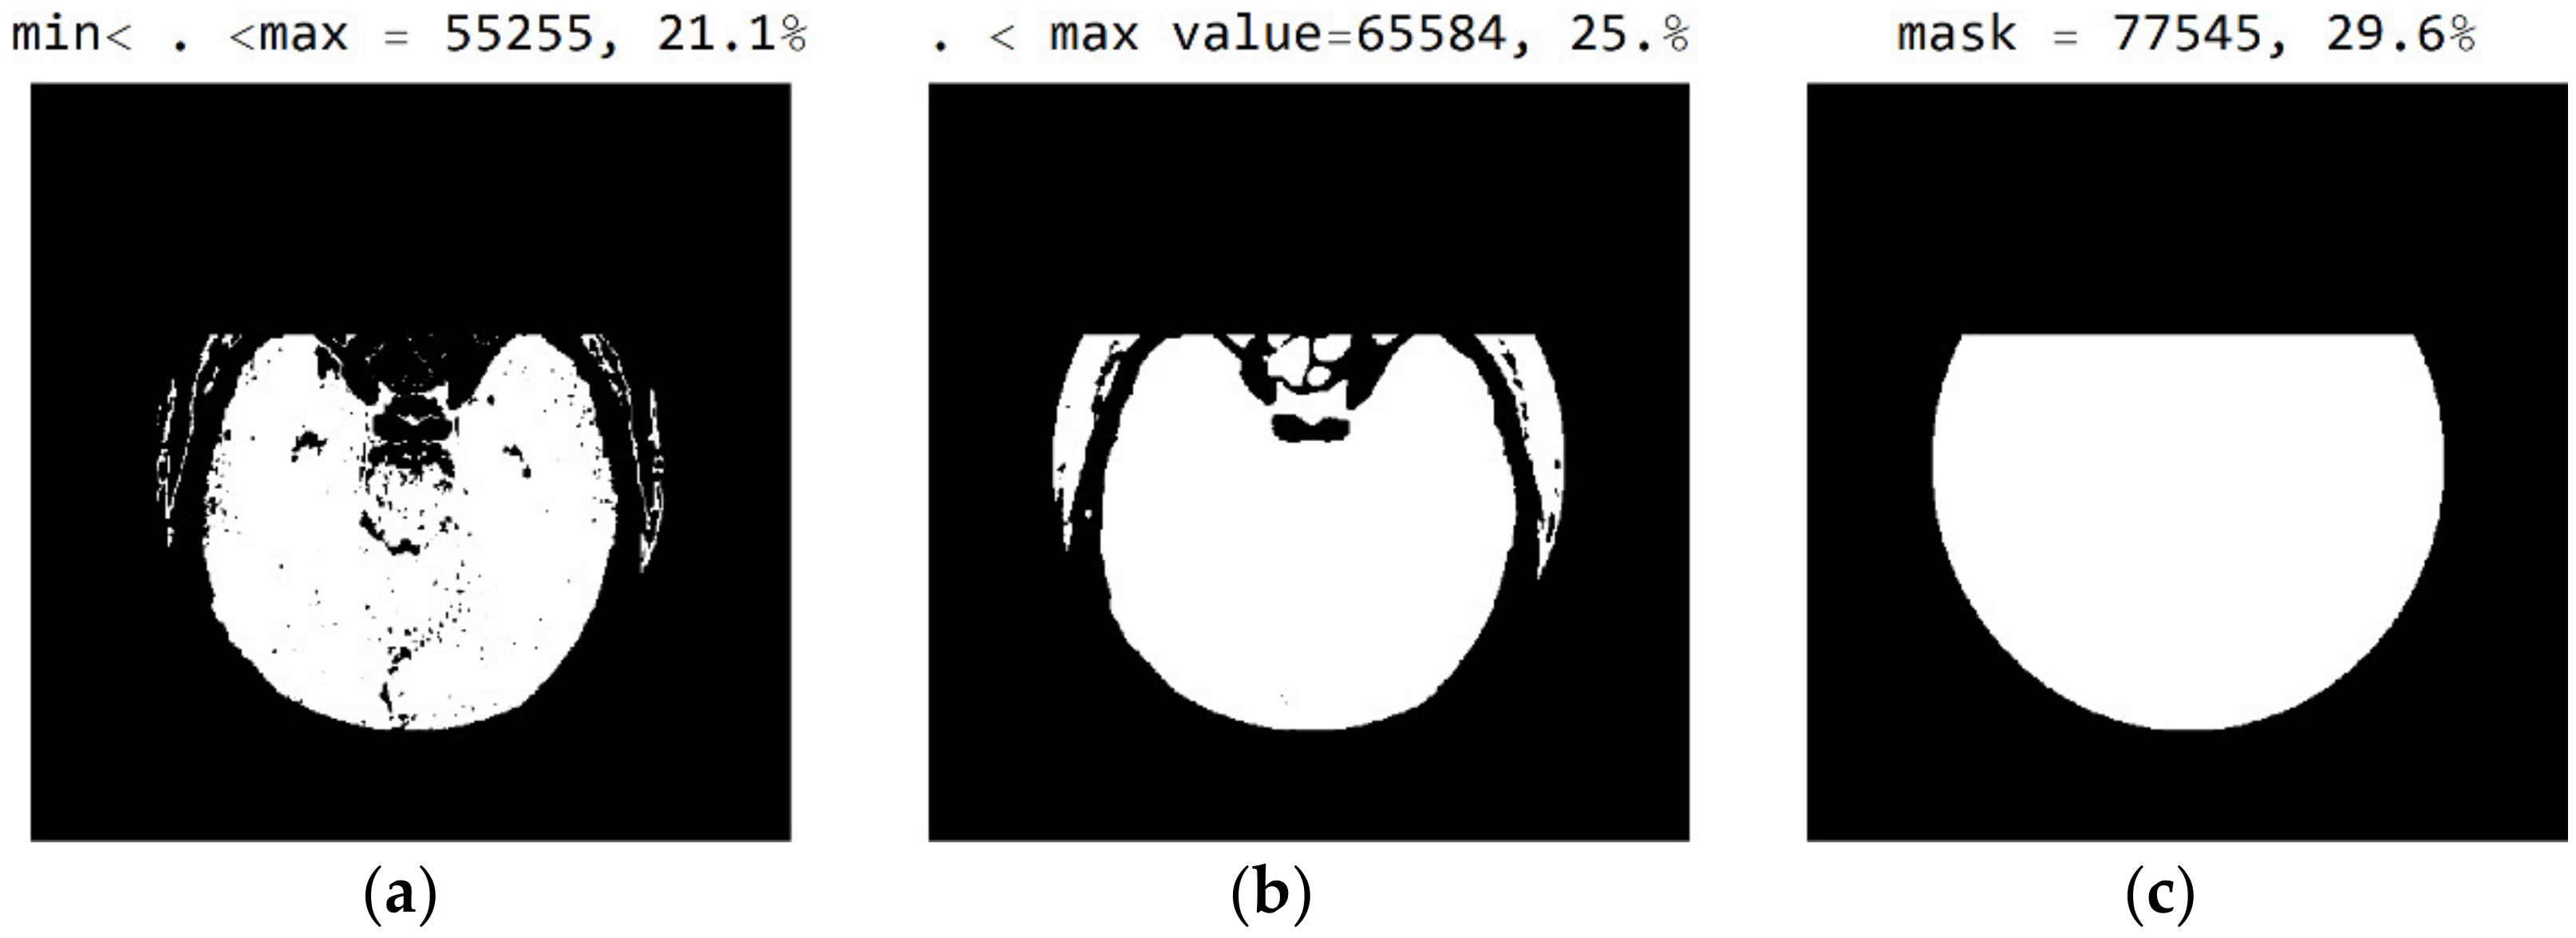

2.2. Smart Visualization Method (SVMI)

3.1. Technological Description